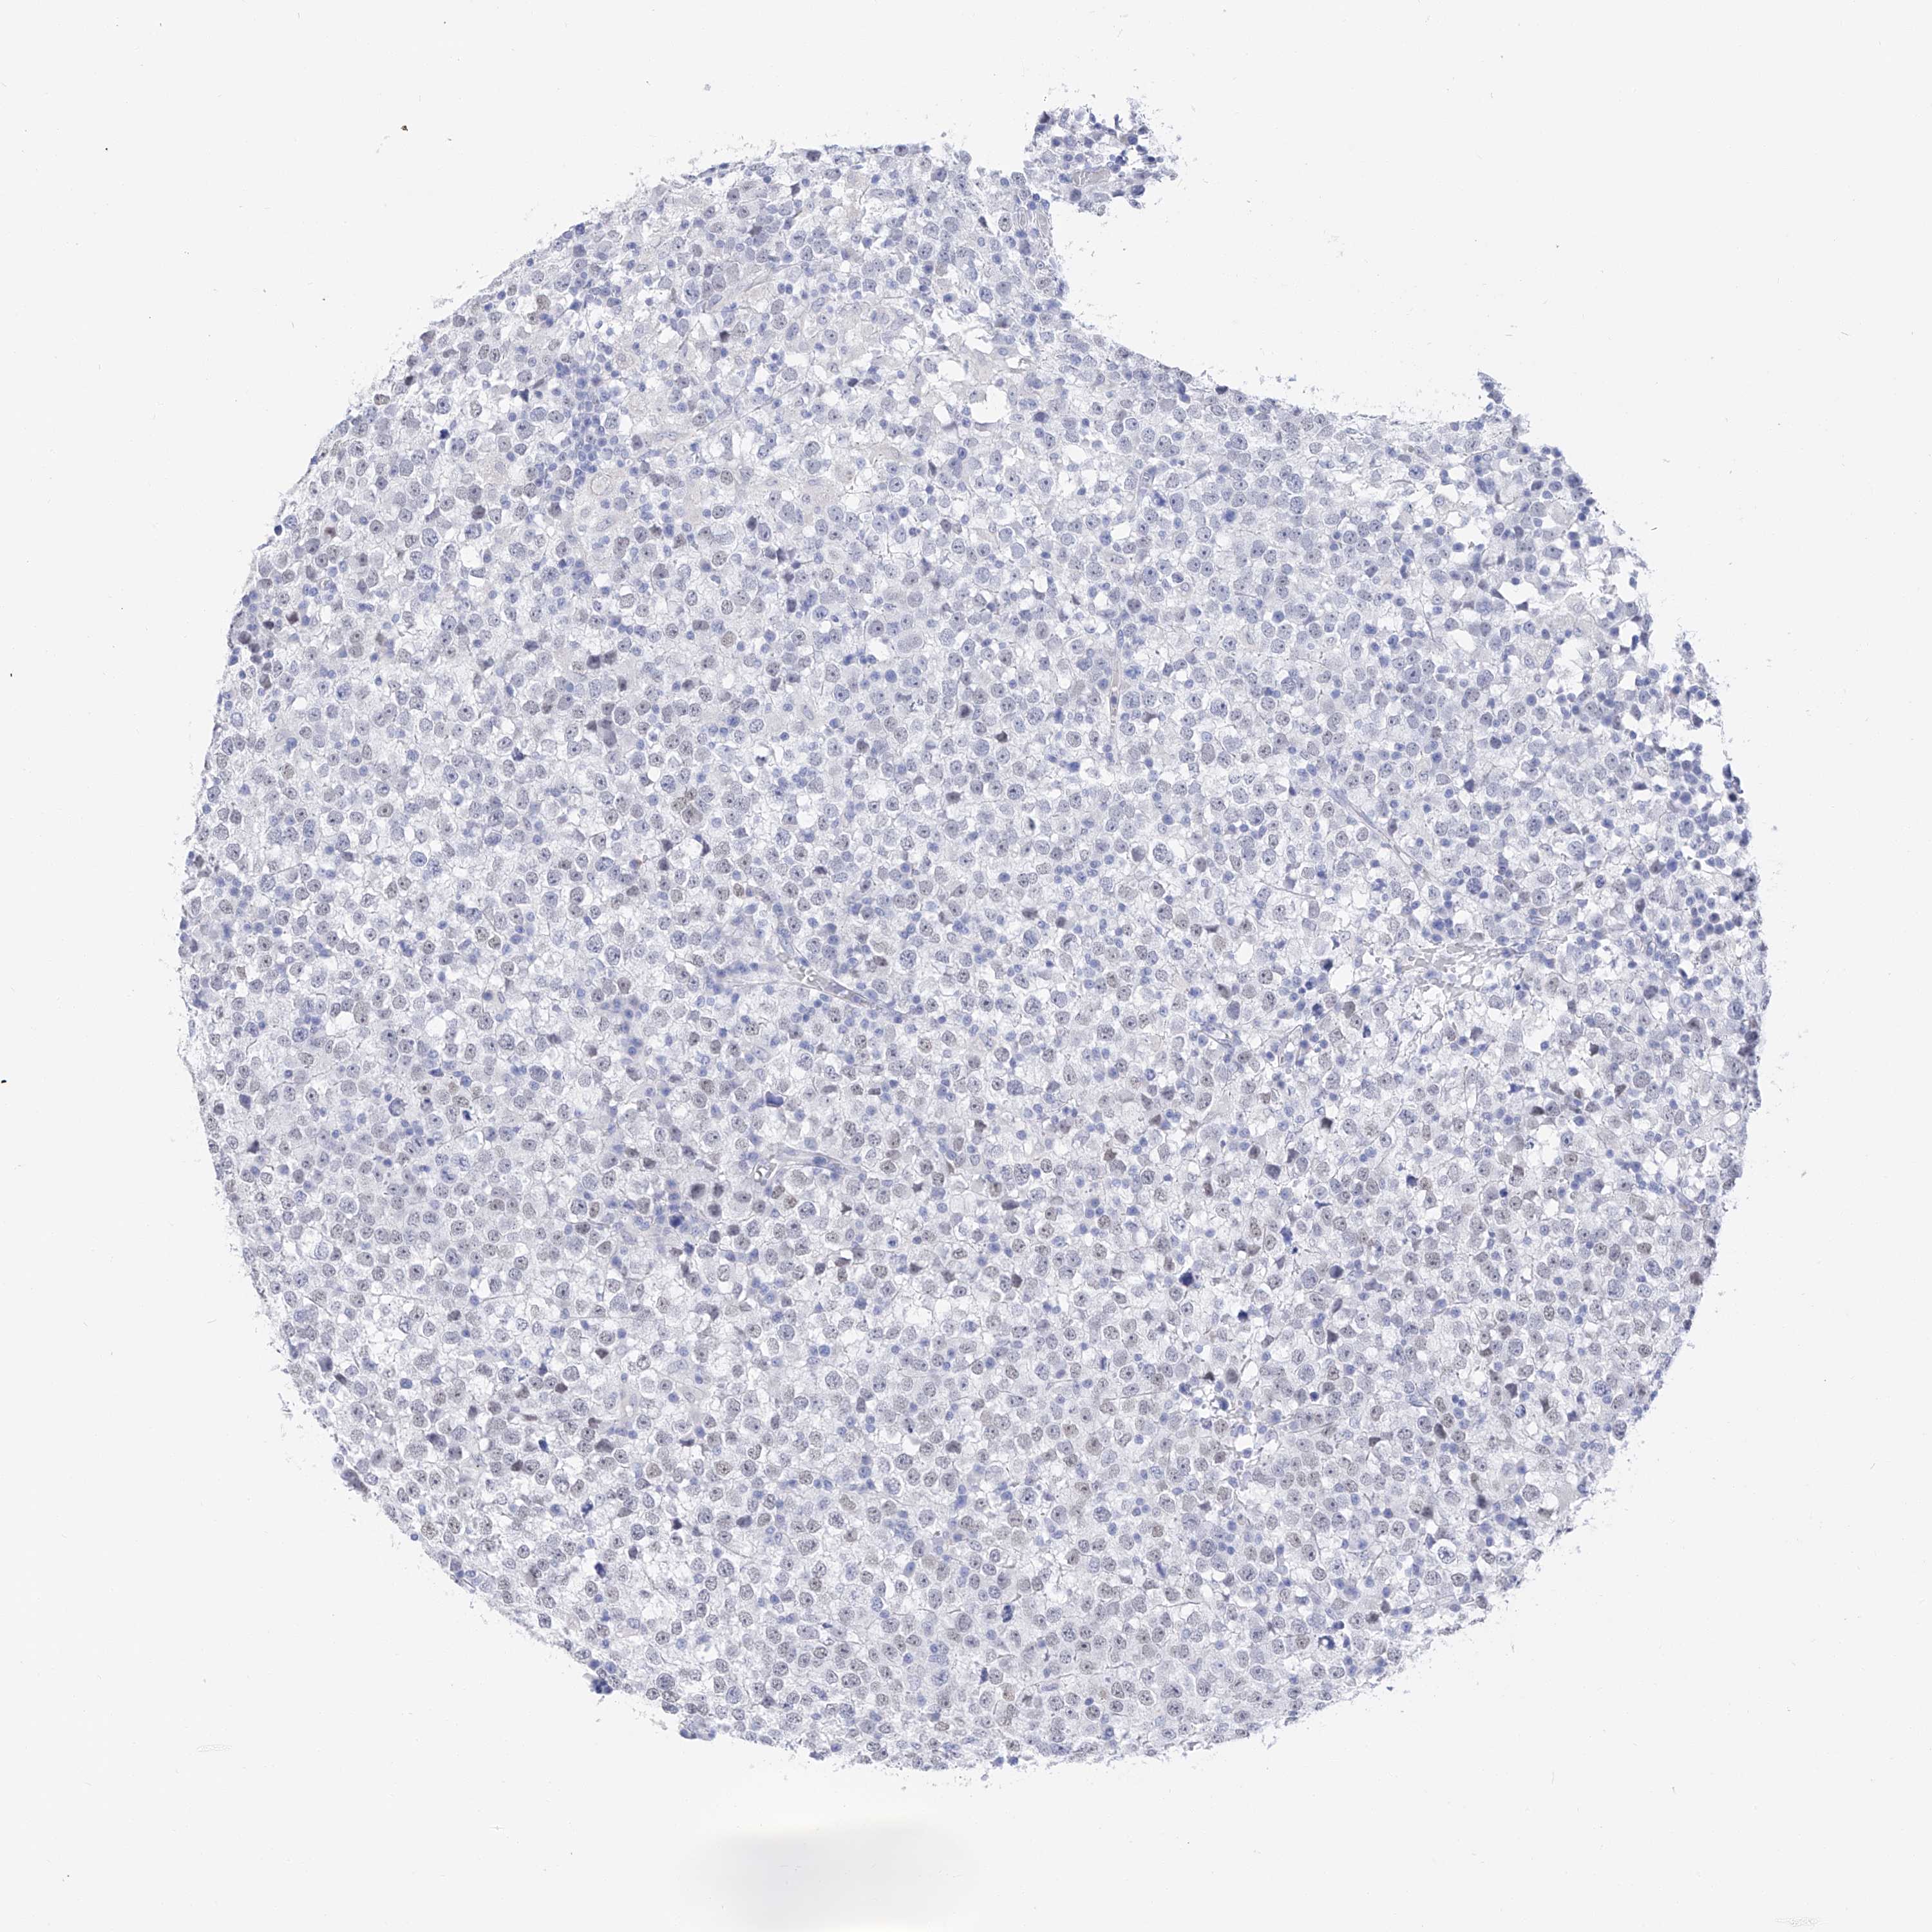

TESTIS CANCER - Protein expressioni

A mouse-over function shows sample information and annotation data. Click on an image to view it in a full screen mode. Samples can be filtered based on level of antibody staining by selecting one or several of the following categories: high, medium, low and not detected. The assay and annotation is described here.

Note that samples used for immunohistochemistry by the Human Protein Atlas do not correspond to samples in the TCGA dataset.

Antibody stainingi

Antibody staining in the annotated cell types in the current human tissue is reported as not detected, low, medium, or high, based on conventional immunohistochemistry profiling in selected tissues. This score is based on the combination of the staining intensity and fraction of stained cells.

Each image is clickable and will lead to virtual microscopy that enables deeper exploration of all samples and also displays staining intensity scores, fraction scores and subcellular localization as well as patient and tissue information for each sample.

Antibody HPA030188

Antibody HPA030189

Antibody CAB002210

Carcinoma, Embryonal, NOS

Seminoma, NOS